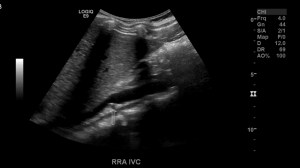

The renal arteries are paired blood vessels that arise from the mid aorta. The right renal artery is typically longer than the left due to the anatomical location of the aorta being more lateral to left of the body. It courses behind the IVC, which can be used as a window in difficult patients.

As stated before the RRA will be located posterior to the IVC. The LRV will be sandwiched between the Aorta and SMA.